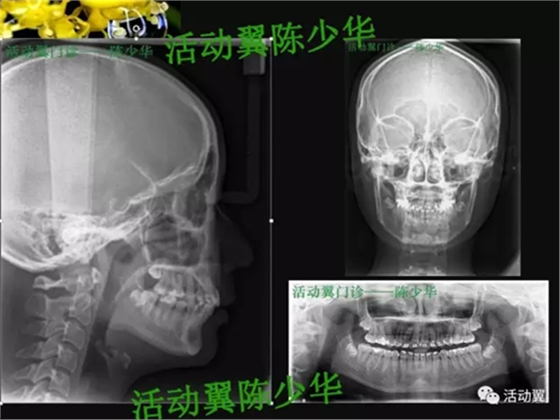

•主訴:上牙前突,上下牙不齊,要求矯正。•牙列檢查:年輕恒牙17-27、37-47。磨牙尖牙遠中關(guān)系;前牙覆蓋6MM,深覆合2度,上牙前傾,下前牙輕度擁擠,Spee曲深。•面型:直面型。下頜輕度后縮。上下頜骨突度正常。顳下頜功能檢查未發(fā)現(xiàn)明顯異常。